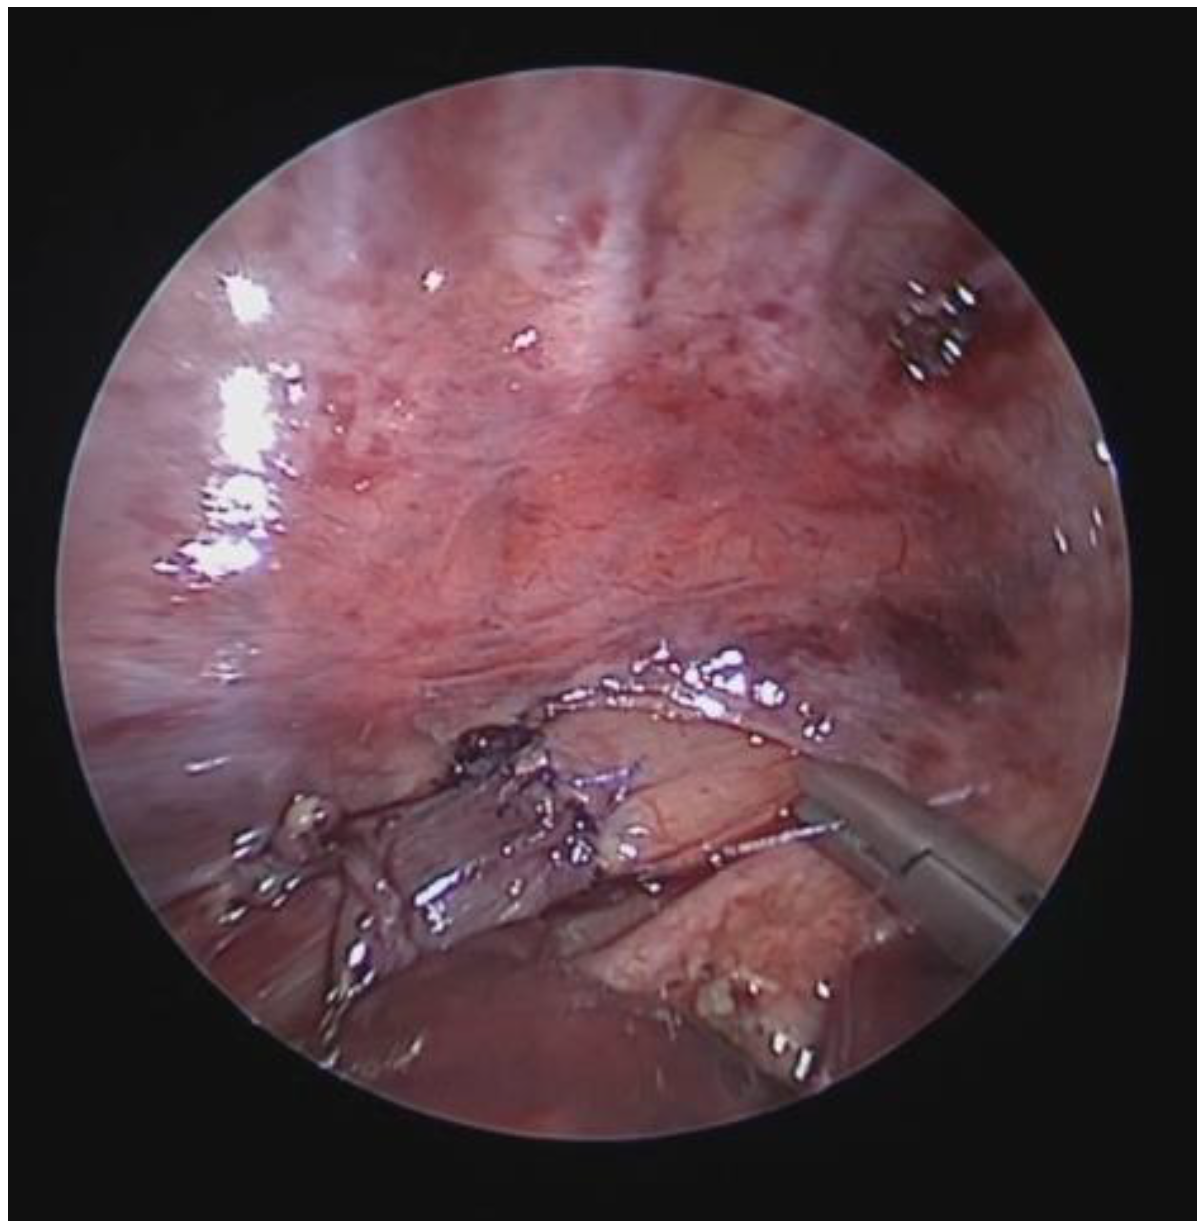

| Score: 2 | Reduction in the APD of the trachea between 75% and 90% compared to the suprastenotic tract and/or anterior tracheal wall and pars membranacea, tending to touch, without complete closure of the lumen, even when the patient performs abdominal straining, with poor representation of the cartilaginous rings. Figure 1, score 2 |